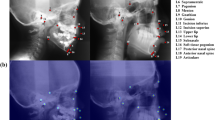

The objective of this work is to present a novel technique using convolutional neural network (CNN) architectures for automatic segmentation of sella turcica (ST) on cephalometric radiographic image dataset. The proposed work suggests possible deep learning approaches to distinguish ST on complex cephalometric radiographs using deep learning techniques.

The dataset of 525 lateral cephalometric images was employed and randomly split into different training and testing subset ratios. The ground truth (annotated images) represents pixel-wise annotation of the ST using an online annotation platform by dental specialists. This study compared convolutional neural network architectures based on fine-tuned versions of the VGG19, ResNet34, InceptionV3, and ResNext50 architectures to select an appropriate model for autonomous segmentation of the nonlinear structure of ST.